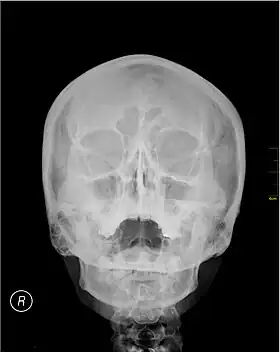

Waters' view | |

![]() A Waters' view radiograph showing the paranasal sinuses | |

Waters' view (also known as the occipitomental view) is a radiographic view of the skull. It is commonly used to get a better view of the maxillary sinuses. An x-ray beam is angled at 45° to the orbitomeatal line. The rays pass from behind the head and are perpendicular to the radiographic plate. Another variation of the waters places the orbitomeatal line at a 37° angle to the image receptor. It is named after the American radiologist Charles Alexander Waters.

Waters' view can be used to best visualise a number of structures in the skull.

- Maxillary sinuses.

- Frontal sinuses, seen with an oblique view.

- Ethmoidal cells.

- Sphenoid sinus, seen through the open mouth.

- Odontoid process, where if it is just below the mentum, it confirms adequate extension of the head.

Typically, the x-ray beam is angled at 45° to the orbitomeatal line.[3] Another variation of the waters places the orbitomeatal line at a 37° angle to the image receptor,[4] or 30°.[5]